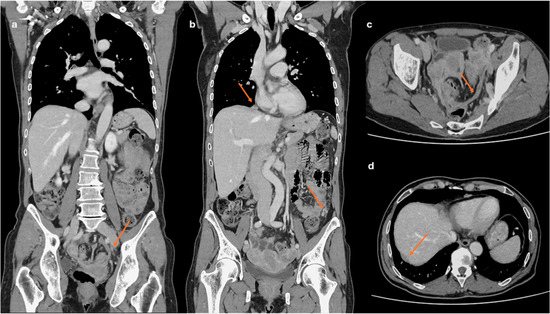

Background/Objectives: Extramedullary involvement in multiple myeloma represents an aggressive disease phenotype, associated with reduced survival and an unfavorable prognosis. Thoracic manifestations are rare and remain poorly characterized in the literature. Methods: We conducted a retrospective, single-center study at the Fundeni Clinical Institute, including patients diagnosed with multiple myeloma between February 2010 and February 2025. The study cohort consisted of 34 patients with infiltration of the pulmonary parenchyma, pleura, or the presence of myelomatous pleural effusion. Diagnosis was confirmed using a combination of imaging modalities (computed tomography or magnetic resonance imaging), cytological examination, immunophenotyping, and histopathological confirmation whenever feasible. Results: Out of a total of 2012 patients with multiple myeloma, the incidence of pleuro-pulmonary extramedullary involvement was 1.6%. The median age at diagnosis was 58 years. Pleuro-pulmonary disease was present at initial diagnosis in 26.5% of cases, while 73.5% developed it at relapse. The most common presentation involved combined pleural involvement and myelomatous effusion (70.6%). Adverse prognostic markers included elevated β2-microglobulin levels (in over 80% of cases) and increased lactate dehydrogenase (LDH) in approximately 50%. Cytogenetic abnormalities such as del(17p), t(4;14), t(14;16), t(11;14), and 1q gain were identified. The median overall survival (OS) from the diagnosis of pleuro-pulmonary extramedullary disease was 16 months, with a 2-year survival rate of 25%. No patient survived beyond 5 years. The median progression-free survival (PFS) was 9 months. Conclusions: Our findings confirm the aggressive clinical course and poor prognosis of these disease manifestations, mainly when they occur at relapse. In the absence of standardized treatment guidelines, individualizing therapy and accessing novel strategies may be essential for improving patient survival.